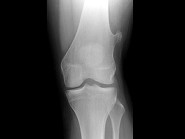

- 单项选择题女,39岁。发现左大腿下段后部有一肿块, 质较硬,无明显疼痛感觉, 结合所提供的图像,最可能的诊断是 ( )

A、软骨肉瘤

B、软骨瘤

C、骨肉瘤

D、骨软骨瘤

E、骨瘤